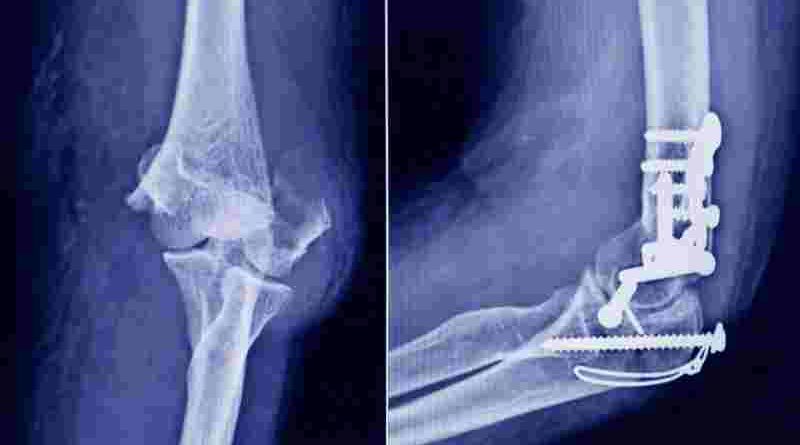

La Administración Nacional de Medicamentos, Alimentos y Tecnología Médica (ANMAT) advirtió a la población por un tornillo utilizado en cirugías traumatológicas debido a que es falso, por lo que su uso representa riesgo para la salud del paciente al que se lo implante.

Se trata de un tornillo utilizado en cirugías traumatológicas que fue detectado durante una inspección de control de mercado realizada en una ortopedia ubicada en la ciudad de San Miguel de Tucumán.

Dicho tornillo es producido por la firma Stryker Corporation, que se encuentra registrada ante ANMAT bajo el PM 594-139. Luego de la inspección, se exhibió la muestra recolectada ante la responsable técnica de dicha empresa, quien afirmó que se trataba de un producto falsificado.

Las autoridades de la ANMAT dieron a conocer las características del producto para su advertencia: STRYKER 10 mm X 28 mm – BIOABSORBABLE – ACL INTERFERENCE SCREW – REF 234-010-067 – LOT 90905.

Al tratarse de un producto falsificado, se desconoce el origen, composición, seguridad y aptitud del producto mencionado, por lo que su uso representa riesgo para la salud del paciente a quien se lo implante.